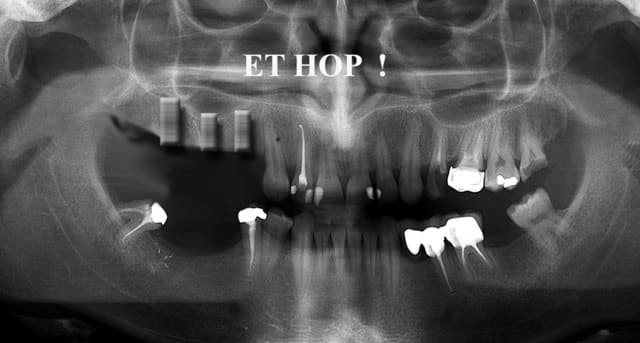

homme, 33 ans, super motivé pour une réhabilitation complète.

comme vous pouvez le constater sur le modèle en plâtre et à la différence de l'opt de départ; 18/48 et 28 ont été extraites.

j'attends vos propositions de traitements...